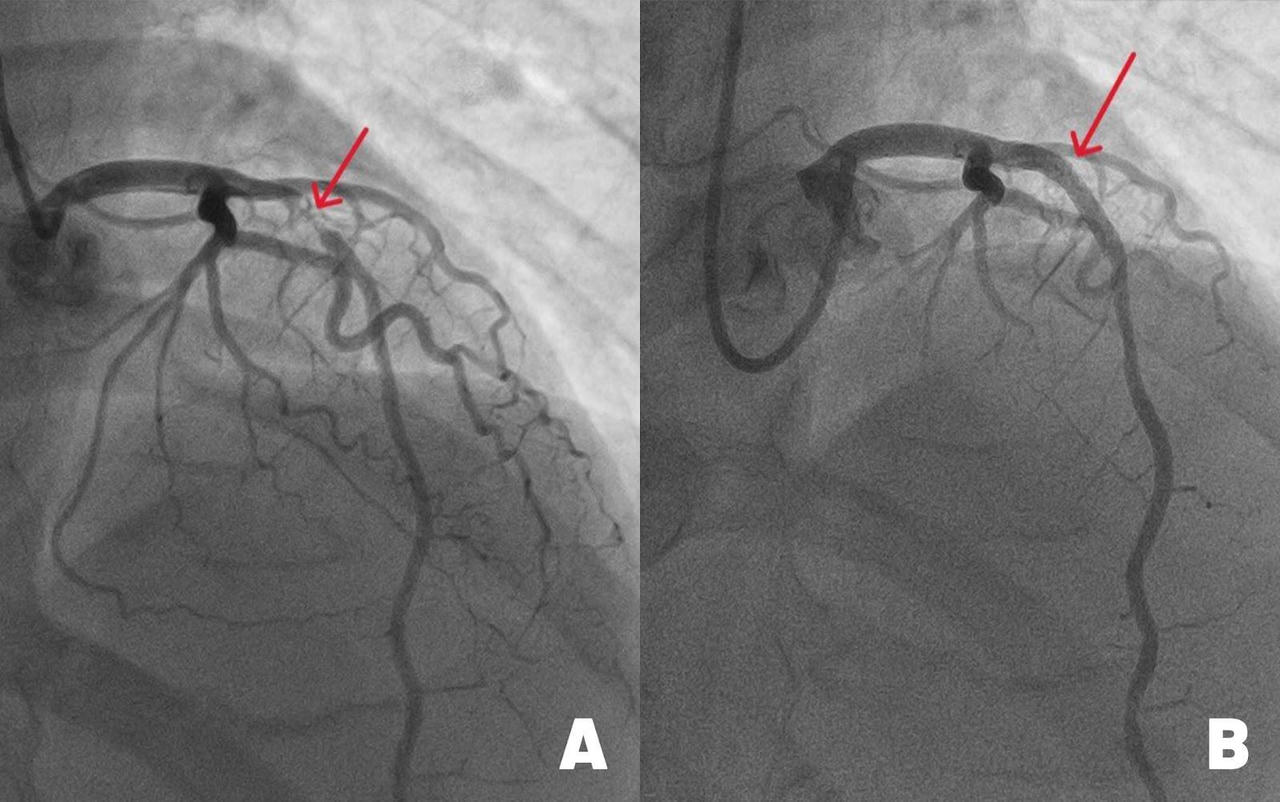

Hình ảnh động mạch liên thất trước (mạch máu chính nuôi tim) bị đứt do tắc nghẽn nặng (hình A) và sau khi được tái thông nhờ đặt stent kích thước lớn. Ảnh: BVĐK Tâm Anh

Kết quả chụp mạch vành cho thấy, động mạch liên thất trước hẹp đến 99%. May mắn là vẫn có một dòng chảy nhỏ giúp cầm cự, tưới máu tạm thời nuôi cơ tim. “Với tình trạng này, cần can thiệp đặt stent càng sớm càng tốt cho bệnh nhân để tái thông dòng máu, tránh nguy cơ đột quỵ tim có thể xảy đến bất cứ lúc nào”, bác sĩ Long cho biết.

Với kinh nghiệm xử lý những ca hẹp nặng mạch vành, bác sĩ Long và êkip luồn ống thông từ động mạch quay (ở cổ tay) tới chỗ xuất phát động mạch vành trái. Sau đó, luồn sợi dẫn 0.35mm qua vị trí hẹp ở động mạch liên thất trước. Dưới sự hỗ trợ của hệ thống siêu âm trong lòng mạch (IVUS), êkip đo đạc chính xác đường kính mạch máu, đặt một stent phủ thuốc, nong nở rộng lên đến 4.0 mm, áp sát thành mạch, ngăn nội mạc mạch máu tăng sinh quá mức. Điều này giúp giảm nguy cơ tái hẹp trong stent, tái phát nhồi máu cơ tim xuống thấp (dưới 2%).